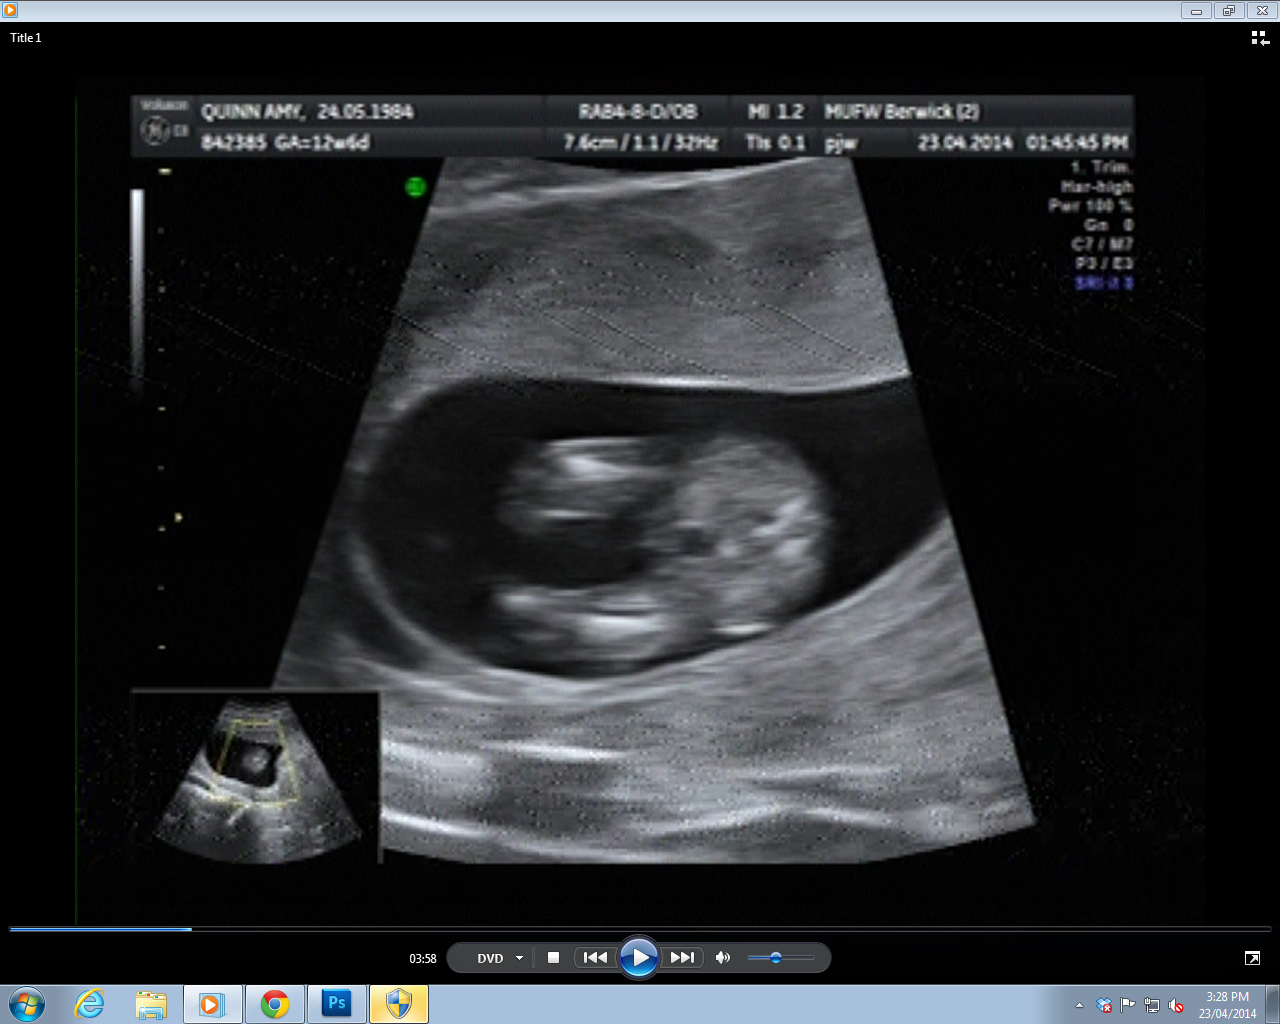

Potty shot 1 - I can just see a protopenis in this one, although it's as blurry as...

Attachment 18366